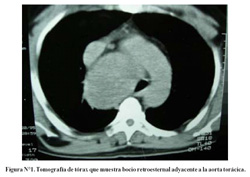

Una tomografía de tórax (Figura N°1) muestra que la tumoración cervical se extiende hasta el mediastino superior, con compresión y desviación de traquea cervical y torácica. Otros estudios rutinarios pre-operatorios de laboratorio fueron normales. Una biopsia por aspiración con aguja mostró ocasionales células foliculares tiroideas con presencia de material coloide. El paciente fue sometido a intervención quirúrgica iniciándose con una incisión cervical en collar, la cual luego se extendió inferiormente con una esternotomía mediana total. Se halló una tumoración gigante con origen en el lóbulo derecho tiroideo, anterior a la tráquea y al cayado aórtico; y posterior a la vena innominada. Se realizó una hemitiroidectomía derecha, en un tiempo de 4 horas 30 minutos, con un sangrado intraoperatorio de 1 500 mL, requiriendo transfusión de 3 paquetes globulares. El esternón se cerró con alambre y se colocaron dos tubos de tórax en el mediastino (32 French). El espécimen remitido medía 17 x 11 x 8 cm y pesaba 620 gramos (Figura N°2). El diagnóstico histopatológico final fue bocio coloide. El paciente tuvo evolución favorable, se retiraron los tubos de tórax en el día postoperatorio 5, saliendo de alta 9 días luego de la operación. La disfonía persistió, pero mejoro notoriamente a los 6 meses luego del alta. Un año mas tarde, el paciente continua en buen estado general sin evidencia de recurrencia de la lesión.